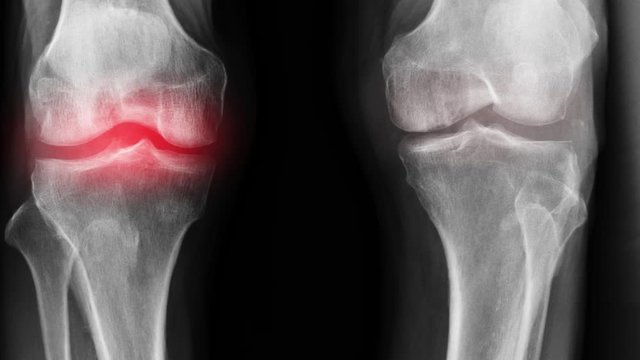

La préparation a été créée à partir de la formule de Sarah Sibanda. Il favorise le processus de guérison du tissu cartilagineux au niveau cellulaire, arrête le processus de détérioration articulaires et élimine la source de l'infection. Le médicament élimine les anomalies dans le liquide synovial et restaure la fonction des articulations, il augmente également la flexibilité des articulations en raison de sa propriété anti-mortification améliorée. On a nommé le produit - Marukaya Cream.

Franz Geisler : Merci à vous. Je voudrais conseiller à tous les lecteurs d'essayer de résoudre leurs problèmes articulaires, car ils sont à l'origine de maladies graves telles que l'arthrite, l'arthrose, la bursite et d'autres maladies dangereuses.